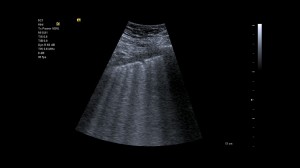

Caption foto: Examinare a plamanului folosind sonda convexa. Se pot observa liniile B ce apar din linia pleurei si se extind spre baza ecranului fara sa se estompeze.Cele mai importante artefacte pentru evaluare sunt liniile A si liniile B. Intr-o imagine cu ultrasunete normala, liniile A apar ca linii de repetare orizontale, paralele ale pleurei. Ele apar cu tesut pulmonar intact si alunecare normala a plamanului (miscarea plamanului la peretele toracic in timpul respiratiei). Daca nu exista alunecare pulmonara, este probabila o colectare anormala de aer in spatiul pleural (pneumotorax). Liniile B ruleaza vertical si indica acumulari de lichid. Mai multe linii B indica edem pulmonar.